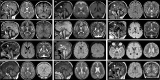

Retinoblastoma (RB) proteins are highly conserved transcriptional regulators that play important roles during development by regulating cell-cycle gene expression. RBL2 dysfunction has been linked to a severe neurodevelopmental disorder. However, to date, clinical features have been described in only six individuals carrying five biallelic predicted loss-of-function (pLOF) variants. To define the phenotypic effects of RBL2 mutations in detail, we identified and clinically characterized a cohort of 35 patients from 20 families carrying pLOF variants in RBL2, including 15 new variants that substantially broaden the molecular spectrum. The clinical presentation of affected individuals is characterized by a range of neurological and developmental abnormalities. Global developmental delay and intellectual disability were observed uniformly, ranging from moderate to profound and involving lack of acquisition of key motor and speech milestones in most patients. Disrupted sleep was also evident in some patients. Frequent features included postnatal microcephaly, infantile hypotonia, aggressive behaviour, stereotypic movements, seizures and non-specific dysmorphic features. Neuroimaging features included cerebral atrophy, white matter volume loss, corpus callosum hypoplasia and cerebellar atrophy. In parallel, we used the fruit fly, Drosophila melanogaster, to investigate how disruption of the conserved RBL2 orthologue Rbf impacts nervous system function and development. We found that Drosophila Rbf LOF mutants recapitulate several features of patients harbouring RBL2 variants, including developmental delay, alterations in head and brain morphology, locomotor defects and perturbed sleep. Surprisingly, in addition to its known role in controlling tissue growth during development, we found that continued Rbf expression is also required in fully differentiated post-mitotic neurons for normal locomotion in Drosophila, and that adult-stage neuronal re-expression of Rbf is sufficient to rescue Rbf mutant locomotor defects. Taken together, our study provides a clinical and experimental basis to understand genotype-phenotype correlations in an RBL2-linked neurodevelopmental disorder and suggests that restoring RBL2 expression through gene therapy approaches might ameliorate some symptoms caused by RBL2 pLOF.